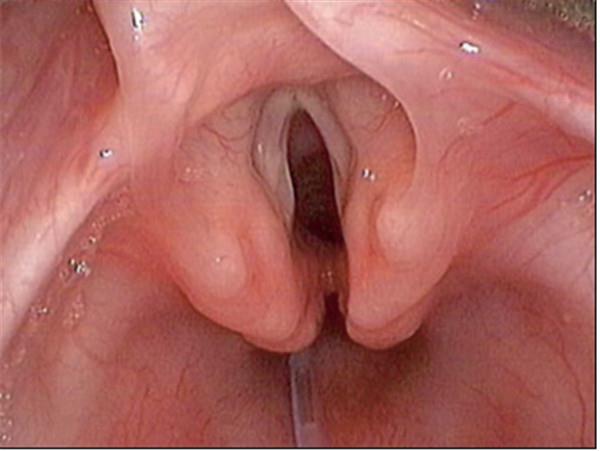

喉裂